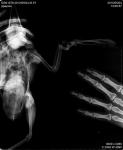

Сегодняшний рентген больного крыла.

post-32872-1430733838_thumb.jpg

Ну....эммм.... кость в месте перелома не срослась... логично, что это доставляет птице боль и дискомфорт. Либо пробовать собирать нормально на спицу отломки, тем более что в данном случае это вполне возможно, либо ампутация.

Вот что говори людям, что не говори, как ПРАВИЛЬНО раскладывать, все равно раскладывают неправильно. А зря. Потому что по рентгену просматривается возможно гепатомегалия и энтерит, а помимо этого похоже что еще и ПУЛЯ от пневматики, которую в любом случае надо извлекать, иначе птицу ждет хроническое отравление тяжелыми металлами.

Но наверняка по такому снимку утверждать не берусь, потому что птицу Вы собрали в комок. Снимок надо переделеать и на этот раз разложить ПРАВИЛЬНО.